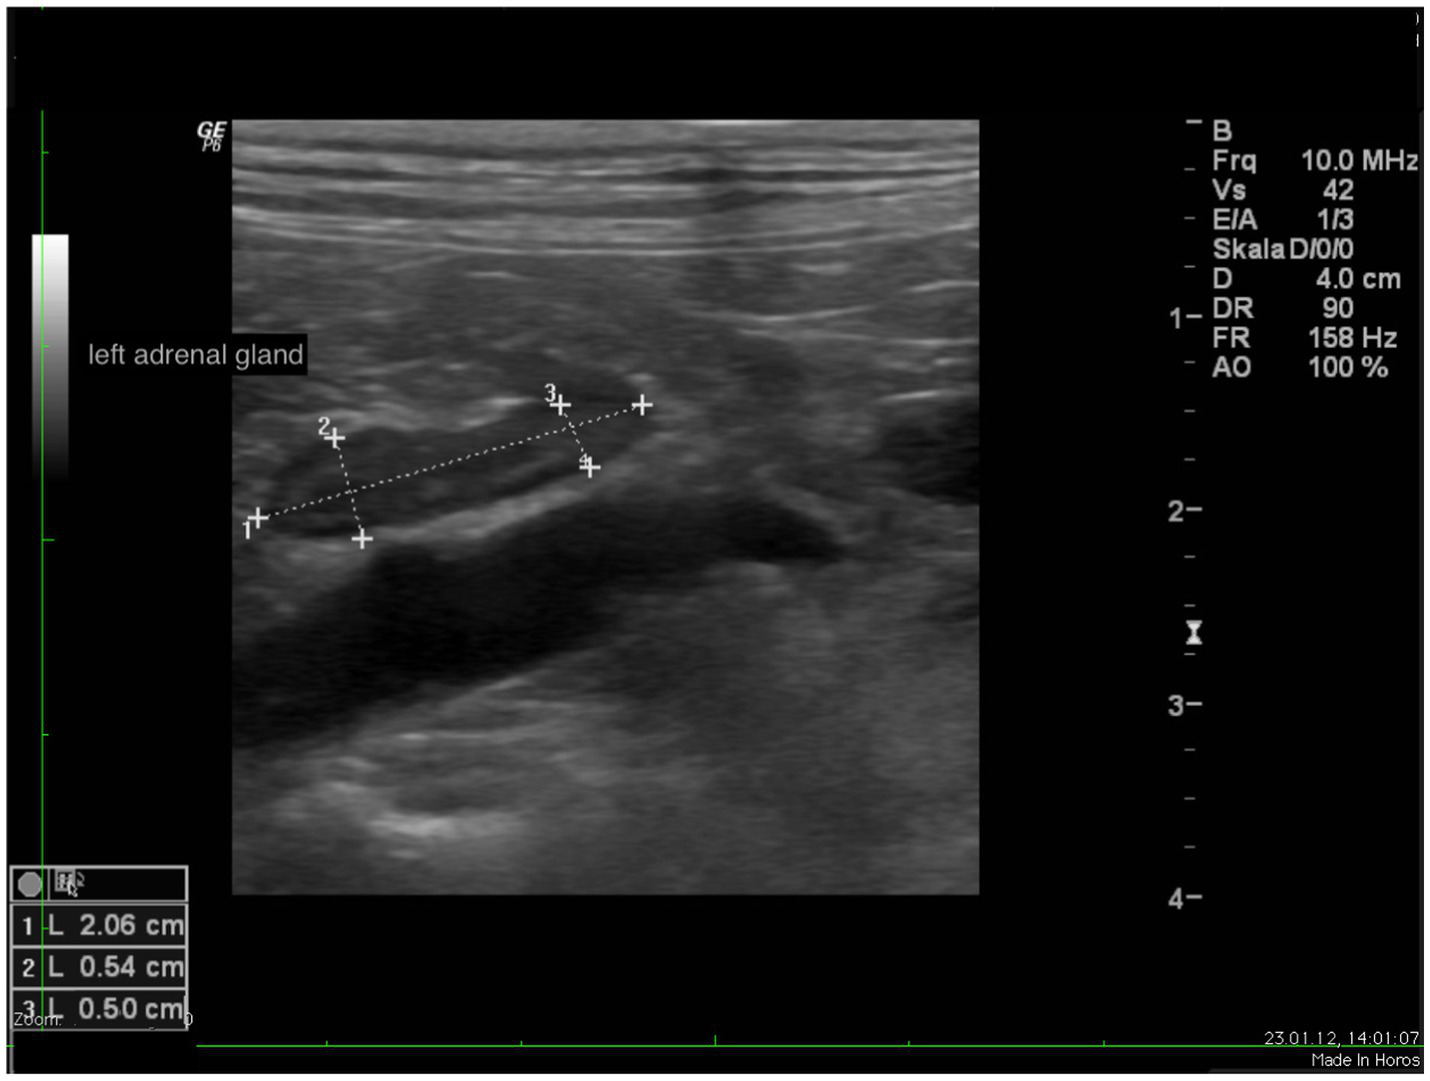

In all dogs the maximum width of the adrenals was measured. The median maximum width of the left adrenal gland was 0.71 cm (IQR, 0.24 cm) and of the right adrenal gland was 0.75 cm (IQR, 0.19 cm). In a subset of dogs, measurements of the cranial and caudal adrenal poles were available. Thirty-eight measurements of the width of the cranial pole and 41 measurements of the width of the caudal pole of the left adrenal glands, and 38 measurements of the width of the cranial pole and 37 measurements of the caudal pole of the right adrenal glands were available. All detail data are shown in Table 6. The median difference between the two poles of the left adrenal gland (n = 37) was 0.11 cm (IQR, 0.12 cm) and of the right adrenal gland (n = 31) was 0.11 cm (IQR, 0.15 cm; Table 6). Figures 2, 3 show the measurement of a left and right adrenal gland. Figure 4 shows the image of the smallest documented adrenal gland.

Figure 2

www.frontiersin.org

Figure 2. Ultrasound image of the left adrenal gland with measurement of the cranial and caudal pole (0.54 and 0.5 cm, respectively).